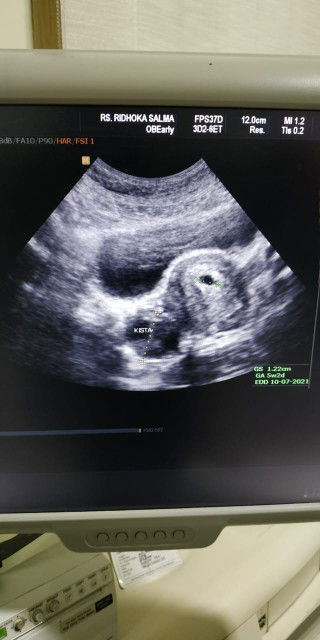

Maaf bunda mau tanya. Sya sdg hamil 6 minggu, anak pertama. Dan stlh d USG ternyata sya jg ada kista

Kista sbsar 3cm apakah berbahaya? Bagi janin dan ibu?#seriusnanya #firstbaby #1stimemom mohon pencerahannya